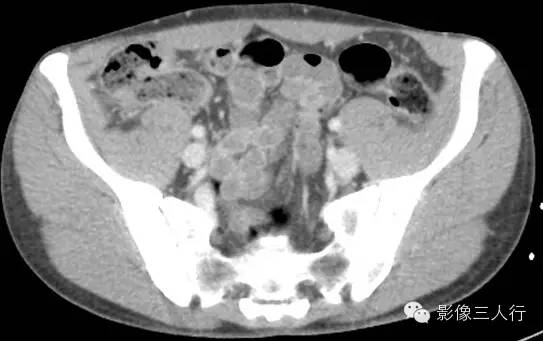

延盲肠层面向下延续能看到腹股沟管走行区可见到管状的阑尾影像,腔内可见气体密度,阑尾壁无增粗,周围无明显渗出。